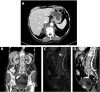

Query (Q) fever is a zoonotic bacterial infection caused by Coxiella burnetii. In a minority of patients, chronic disease can occur after acute infection. Endocarditis and infections of aneurysms or vascular prostheses are the most common forms of chronic Q fever in adults. We report a case of an elderly female patient with chronic Q fever vertebral osteomyelitis at the site of her previous cement vertebroplasty, complicated by paravertebral abscess. Patient treatment required prolonged drainage in addition to the long duration of antibiotic treatment by doxycycline and hydroxychloroquine. Osteomyelitis is a rare clinical presentation in adults with chronic Q fever. However, it is important to consider Q fever in the differential diagnosis of culture-negative osteomyelitis, especially in countries where C. burnetii is endemic, such as Israel.